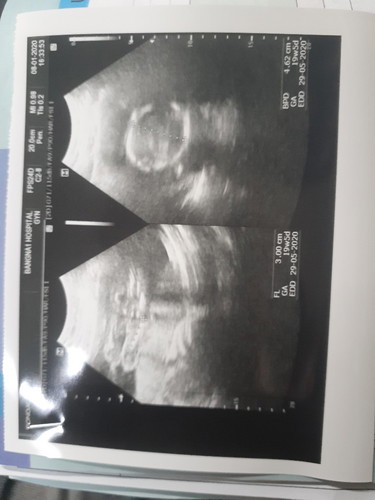

วันนี้ไปซาวน์เพศลูกมา 20weekค่ะ หมอบอกมองยังไม่เห็นเด็กเล็กเกินไป แอบเสียดายค่ะเพราะรอวันนี้นานมาก อยากเห็นเค้าไวๆ บ้านไหนเป็นแบบนี้ไหมคะ แล้วส่วนใหญ่ซาวน์ครั้งต่อไปเห็นไหมคะ